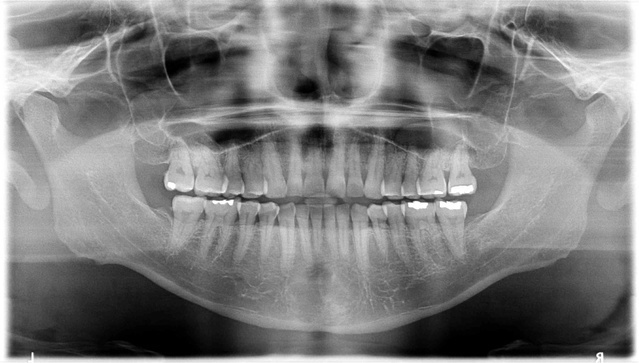

中等度の歯周病のCT画像です。

パノラマ写真(2D)です。パノラマ写真では、1度に歯全体の状態が把握できます。

パノラマ写真(2D)ではわかりにくいですが、CT画像(3D)では、歯周病の進行具合は”みたまま”なので現状を把握するのには理解しやすいとおみます。